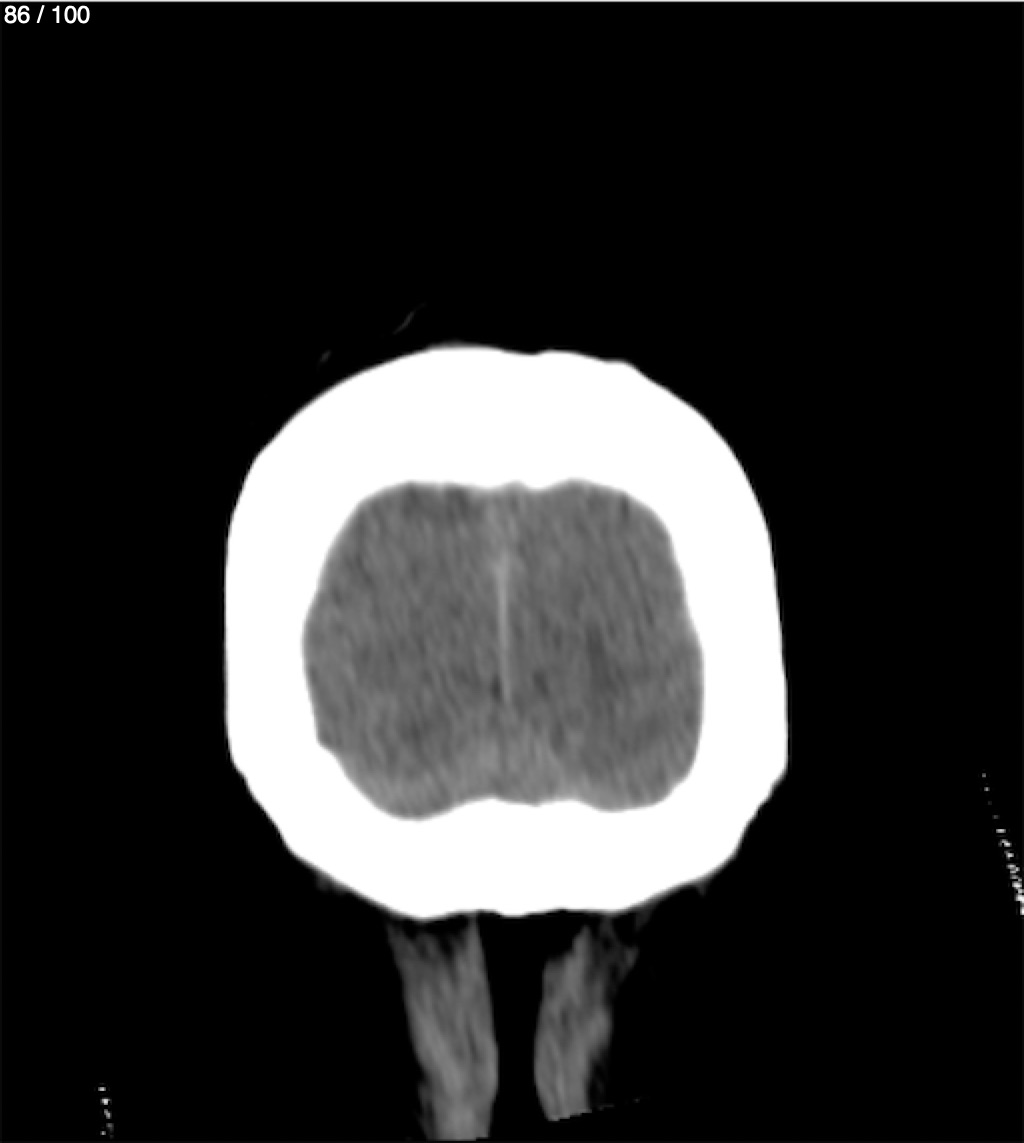

Jose Sosa Martinez 66A - Angiotac Craneo